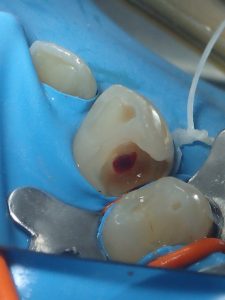

lorsque c’est réalisable ,on tentera de préserver de la vitalité pulpaire!ici c’était pas gagné……….mais…….on a tenté et ça a réussi!

la carie est telle qu’elle atteint la pulpe

on fait une greffe directement sur la pulpe

résultat apres 4 mois :inlay collé pour protéger la biodentine